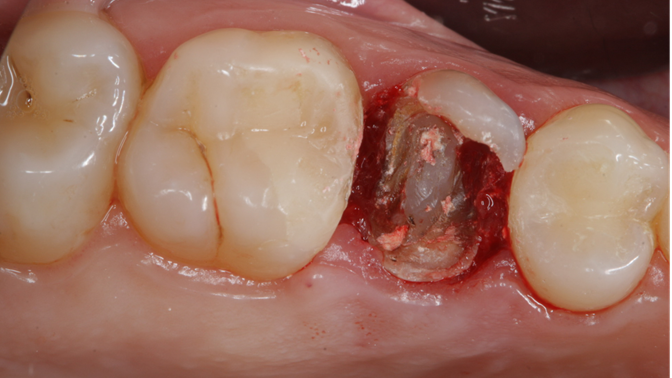

Clinical case: Extraction, immediate implant placement, & provisionalization

- Courtesy of Dr. Iulian Filipov, Romania -

Keywords

AnyRidge, R2GATE, guided surgery, immediate placement, immediate provisionalization, initial stability, Dr. Iulian Filipov, #25, maxillary posterior, immediate loading, Mega ISQ